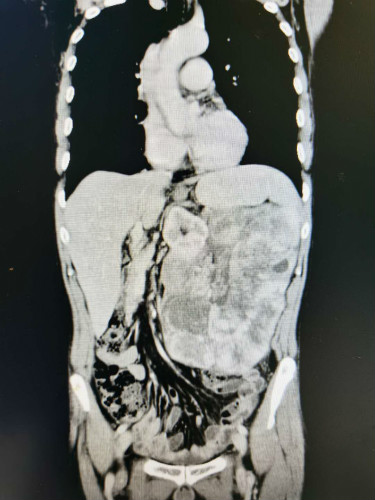

湖南湘阴的周先生因腹胀半月,在当地医院的CT检查结果显示腹膜后占位,考虑腹膜后肿瘤。当地医生建议,此手术难度大、风险高,建议到上级医院寻求最佳治疗。

患者全腹CT

周先生怀着紧张的心情慕名来到湘雅三医院,找到了胃肠外科腹膜后肿瘤专家吴君辉教授。为此,胃肠外科开展术前疑难病例讨论,李小荣教授、吴君辉教授和田步宁医师详细讨论了手术预案。考虑到患者还年轻,团队希望尽办法挽救病人的生命,可以预料到手术难度大、风险高,需要团队拿出外科医生的胆识和担当,确保手术获得成功。